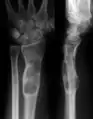

X-ray showing calcified enchondromas localized in finger a 37-year-old patient affected with Ollier disease

X-ray showing enchondromas localized in the humerus of a 37-year-old patient affected with Ollier disease

X-ray showing enchondromas localized in the lower part of the radius of a 37-year-old patient affected with Ollier disease

MRI showing enchondromas localized in the lower part of the radius of a 37-year-old patient affected with Ollier disease

MRI showing enchondromas localized in the lower part of the radius of a 37-year-old patient affected with Ollier disease.

Enchondromas localized in the upper part of the humerus of the same patient